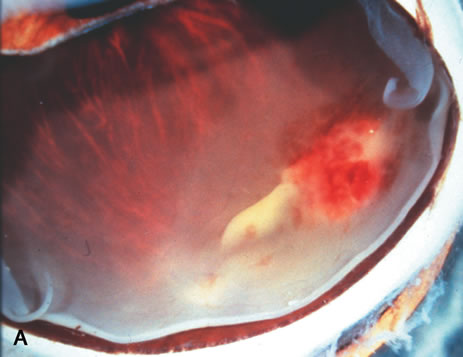

Infectious endophthalmitis refers to inflammation due to an infectious organism, usually bacterial, but it may also be caused by yeast or filamentous fungi. The vitreous is typically involved and supports the growth of the infectious intraocular organism. The reaction to the organism is usually severe and is characterized by abundant polymorphonuclear leukocyte infiltration. The infection is usually accompanied by tissue destruction due to the release of proteolytic enzymes in the severe inflammatory reaction. Uveal and retinal necrosis may occur during these infections. Endogenous endophthalmitis refers to hematogenous dissemination of organisms to the eye and can be seen in cases of septicemia from bacterial or fungal causes. The latter can be caused by Candida or Aspergillus species. Aspergillosis usually causes destructive choroidal inflammation (Fig. 24) with vascular occlusions. The infective organisms are found in the choriocapillaris or along the sub-RPE and sub-retinal space.126

Fig. 24. Aspergillus chorioretinitis. A. Hemorrhagic necrotizing retinitis and choroiditis are noted in a patient with disseminated aspergillosis (hemotoxylin-eosin ×60). B. Note the branching hypae of the organisms involving the retina and choroid (periodic acid–Schiff ×240).